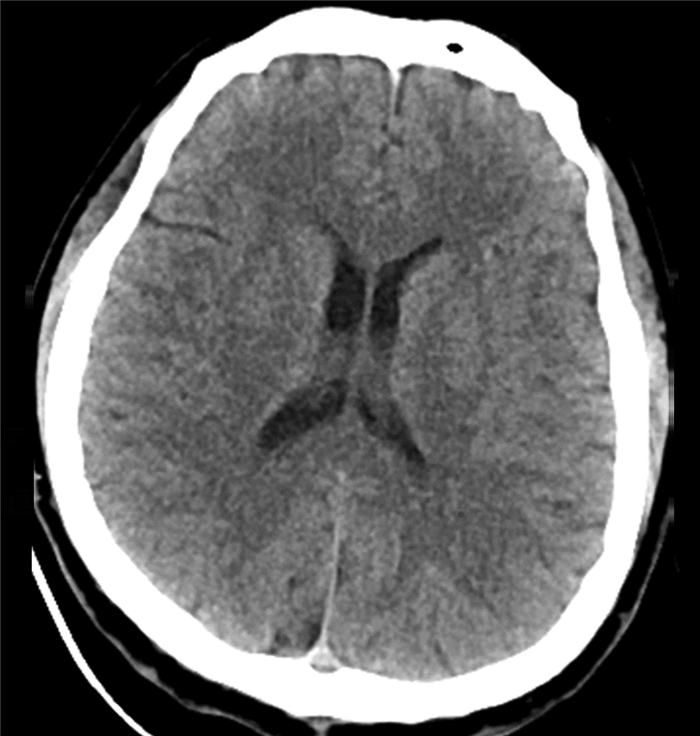

食管胃静脉曲张内镜下治疗后并发可逆性后部脑病综合征1例报告

于亭亭, 姜珊珊, 朱萌然, 白云

2022, 38(1): 177-179. DOI: 10.3969/j.issn.1001-5256.2022.01.030

摘要(816) HTML (198) PDF (3069KB)(57)

摘要: